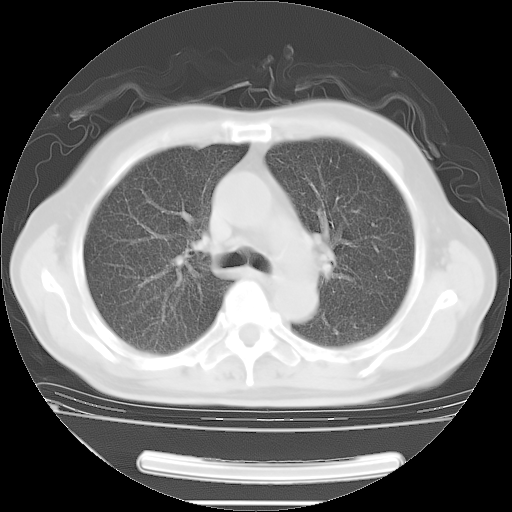

今天复查肺部CT,发现双肺广泛磨玻璃样改变。所以我把3月19日和5月9日相隔50天的肺部CT上传。请大家会诊。

2009年3月19日肺部CT片。

2009年3月19日肺部CT